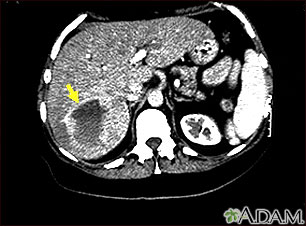

This upper abdominal CT scan shows a blood vessel tumor (hemangioma) in the liver.